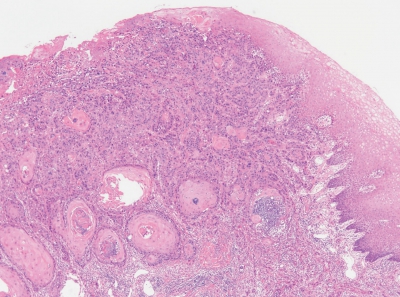

67 歳の男性。下顎前歯部歯肉の腫脹を主訴として来院した。1か月前に気付き、徐々に大きくなってきたという。オトガイ部の感覚に異常はなく、顎下リンパ節とオトガイ下リンパ節の腫脹もない。初診時の口腔内写真、エックス線画像及び生検時の H-E 染色病理組織像を別に示す。

適切な治療法はどれか。1つ選べ。